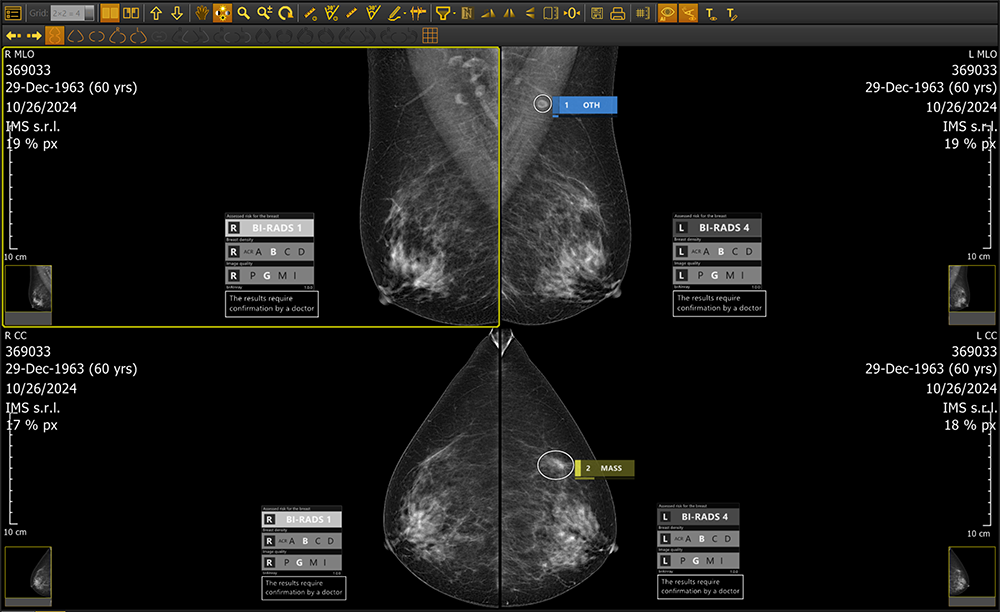

Whether deployed on-site or via the cloud, brAInray® seamlessly integrating with any PACS system, brAInray® analyzes full-field digital mammograms (FFDM) to detect and mark suspicious regions—highlighting calcifications, masses, asymmetries, and architectural distortions. It categorizes findings using ACR BI-RADS® standards and delivers automatic structured DICOM reports for clear, consistent clinical insights.